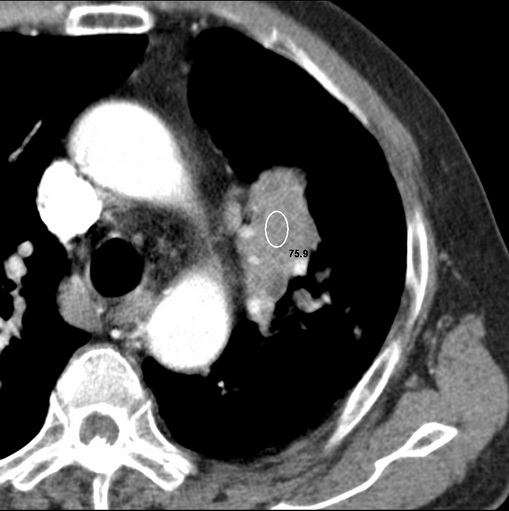

标题: CT25434:胸部CT增强扫描

男性患者 81岁 咳嗽 咳痰 咯血

肿块贴近左肺门,包绕左上肺动脉,形态不规则。肿块增强扫描中度强化。纵膈内主动脉弓左旁间隙、气管隆突前、下间隙见多枚淋巴结影。综上考虑左侧中央型肺癌可能性大。图片没有完整上传,尤其是左肺上叶支气管分支层面没有上传,因此不好判断是叶支气管中断还是段支气管中断。另外,下图红色部分所示是“黏液支气管征”吗?